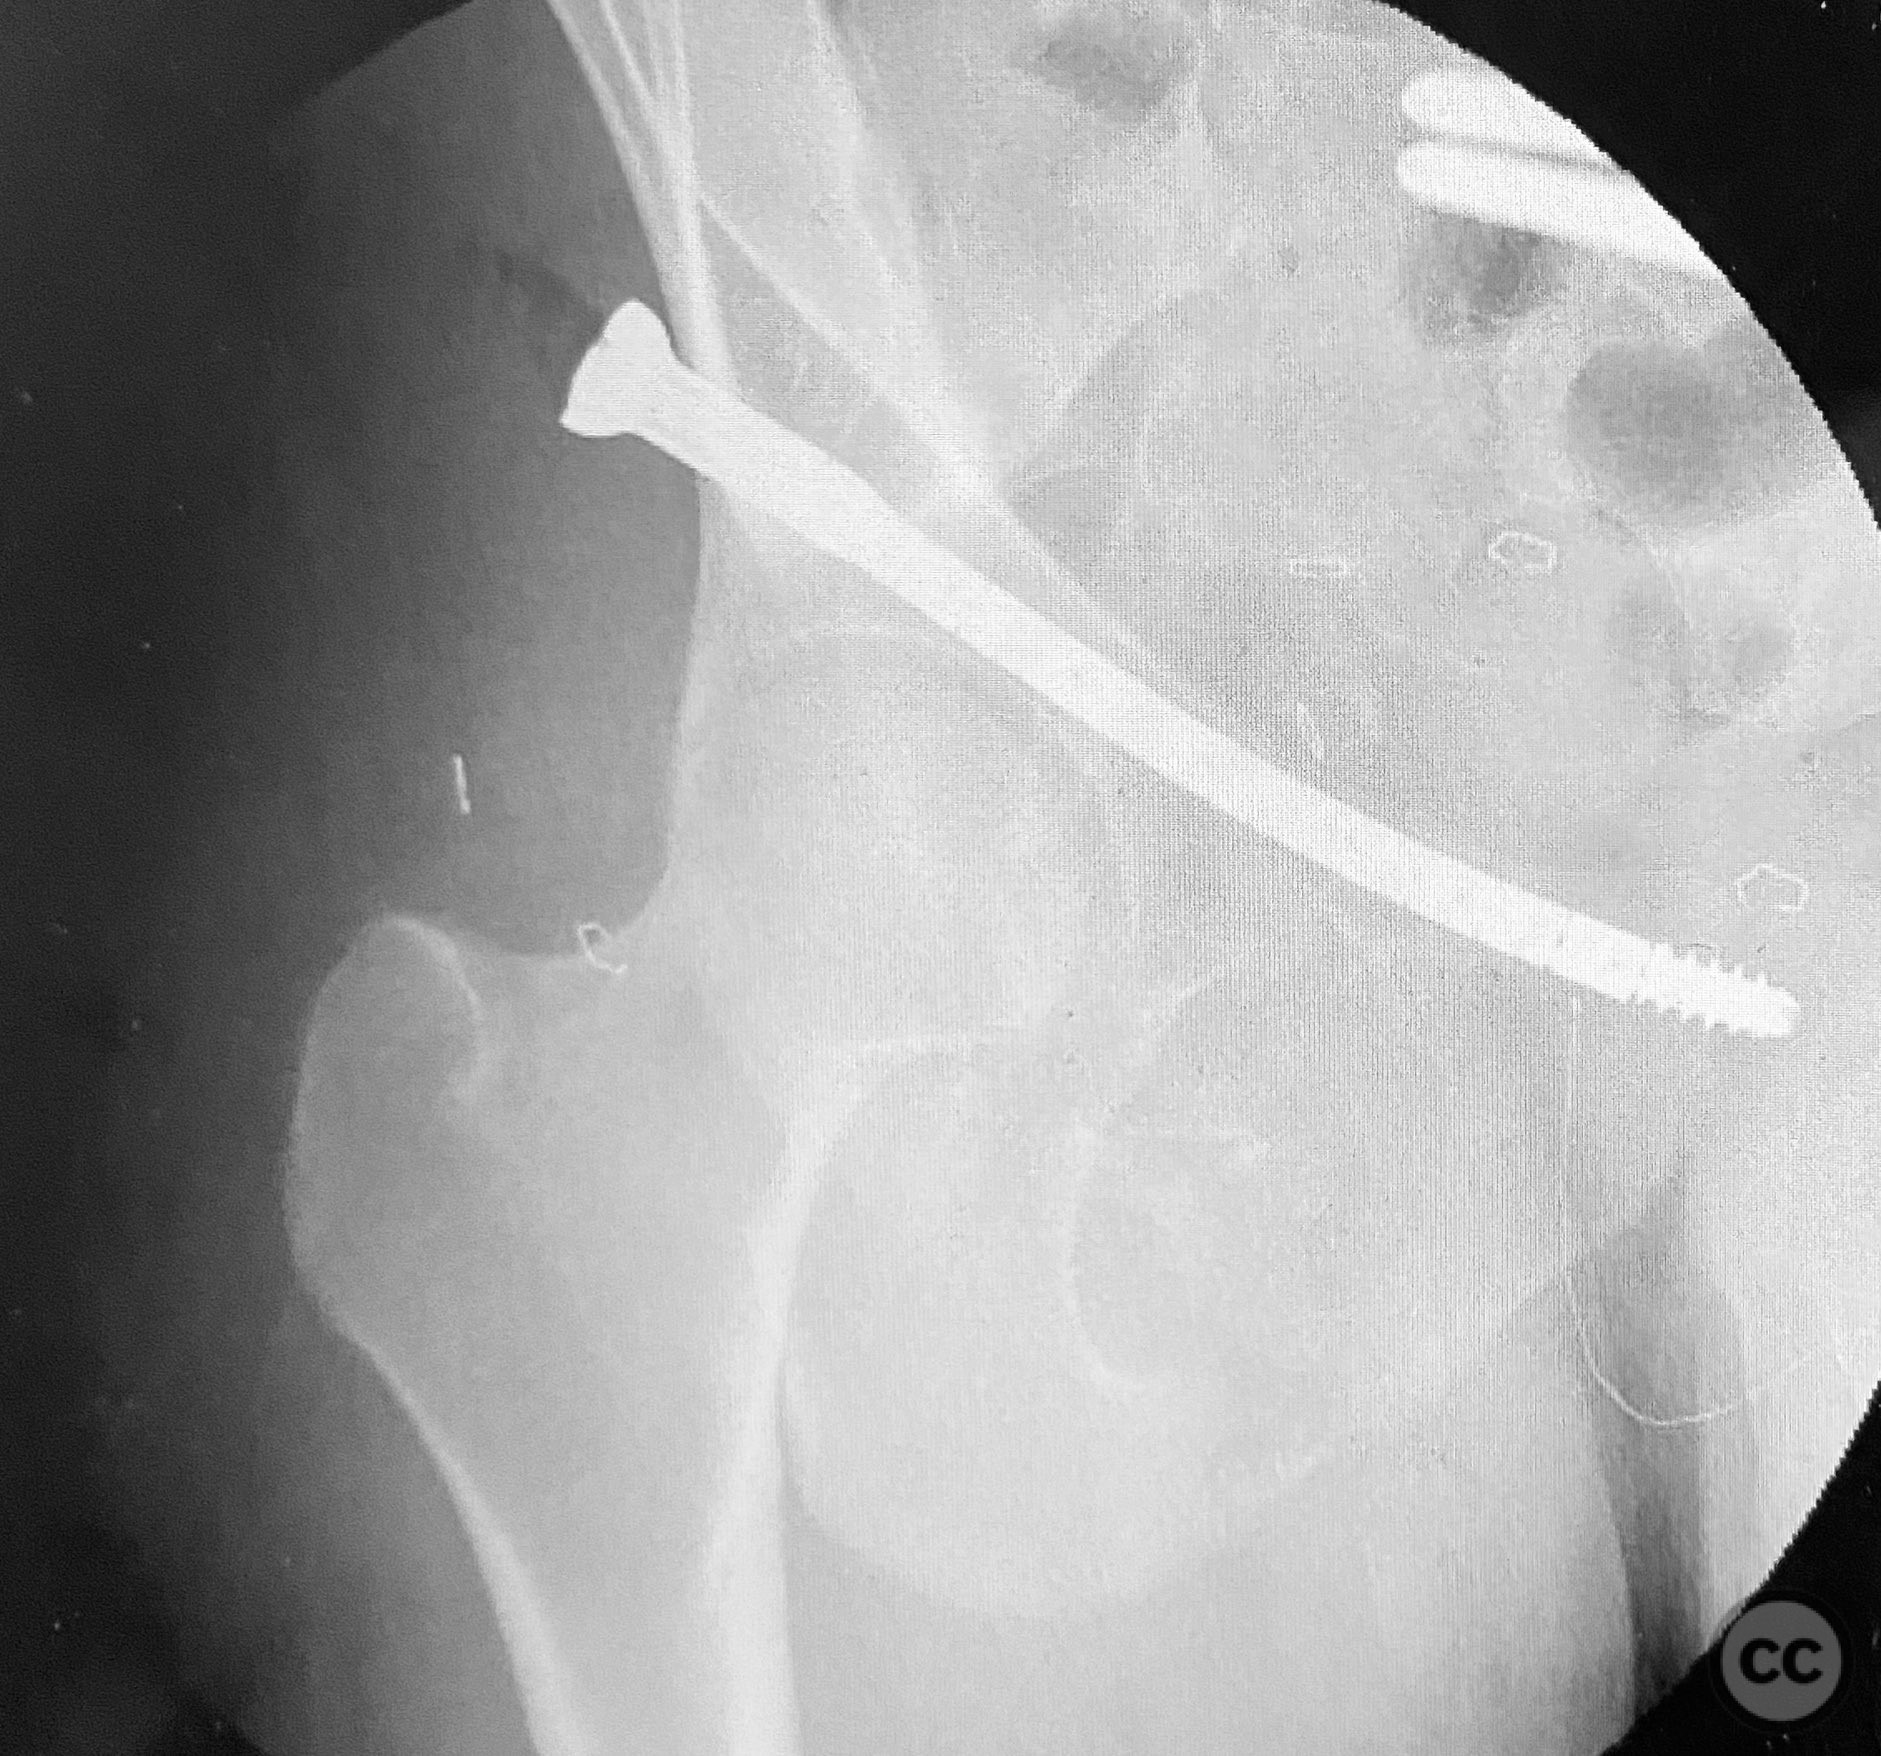

Clinical and radiological findings:  A patient presented with pelvic ring instability and deformity secondary to a left sacral fracture and a right pubic ramus fracture. Imaging demonstrated a displaced left sacral fracture (AO/OTA 61-C1.3) and a right superior pubic ramus fracture, with associated pelvic ring deformity. No neurovascular compromise was noted on initial assessment.

Planning remarks:  The preoperative plan was for closed manipulative reduction of the pelvic ring under fluoroscopic guidance, followed by percutaneous fixation of the right pubic ramus fracture and stabilization of the pelvic ring deformity using a CurvaFix intramedullary device. No open approaches were planned.

Anatomical surgical approach:  A percutaneous approach was utilized. After standard preparation and draping, a small incision was made over the entry point of the right superior pubic ramus. The near cortex was prepared in routine fashion. A curved guide was introduced along the intramedullary pathway of the superior pubic ramus, followed by measurement of required device length. Sequential reaming was performed: first with an opening reamer, then with a pathway reamer to accommodate the device trajectory. The insertion guide wire was exchanged into position, and the CurvaFix device was inserted along the prepared pathway. The device was then locked to achieve rigid fixation.

The application of the CurvaFix device was straightforward. Preparation of the near pathway, insertion of the curved guide, length measurement, reaming, and device insertion proceeded without technical difficulty. The device demonstrated rigid fixation upon locking, even in the presence of comminution at the fracture site.

Orthopaedic implants used:   CurvaFix 130mm length / 7.5mm diameter intramedullary device